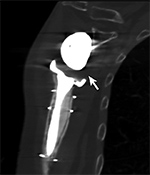

Just as with the immediate post-operative setting, CT is the modality of choice for evaluating complications related to spinal fusion. Screw fracture may occur in up to 25% of patients (Figure 13) (Ohashi, 2009; Lonstein, 1999). As with all cases of hardware failure, the imaging findings should be correlated with patient symptoms as not all hardware complications relate to current clinical symptoms. CT can be useful for the detection of polyethylene dislocation, which may occur in shoulder, hip and knee arthroplasties, and may be difficult to detect on radiographs (Figure 14) (Clarke, 2004).

Figure 11 Figure 12 Figure 13 Figure 14

Hardware infection Small particle disease Hardware failure Liner displacement

Polyethylene Liner Displacement. Sagittal multiplanar reformation of reverse total shoulder arthroplasty demonstrates posteriorly displacement of low attenuation polyethylene liner relative to the humeral component and glenosphere in patient with limited range of motion.